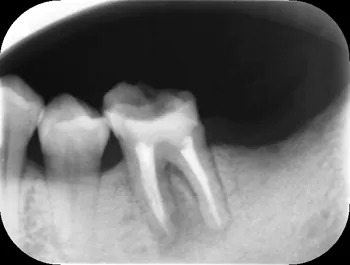

根管充填直後02

| 治療経過 | ラバーダム防湿を行い、マイクロスコープを用いて滅菌下で精密な根管治療を行いました。根管内部を完全にきれいにした後、細菌が繁殖しない様に内部を緊密に封鎖(根管充填)をしました。直後はまだ透過像を認めますが、3ヶ月経過後は炎症もほとんど認められず、症状も改善されていました。 患者さんも抜歯をせずに済んだ為、喜んでいました。現在はラバーダム防湿やマイクロスコープ、また場合によってはCT撮影をする事で今までの治療では見落としていた問題を見つける事ができるようになって、治療の成功率を上げることができます。 |